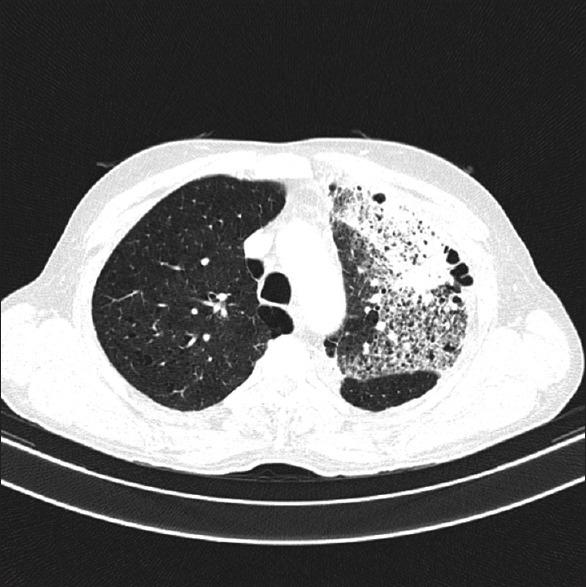

The 'crazy-paving' pattern on high resolution computed tomography (HRCT) is a distinct imaging appearance that is still considered to be a radiological hallmark of pulmonary alveolar proteinosis. However, since its first description about three decades ago, more than 40 different clinical entities presenting as 'crazy-paving' patterns have been documented. This rather remarkable but uncommon imaging appearance is now considered to be a non-specific manifestation. A 62-year-old male referred for evaluation of productive cough, breathlessness and fever presented with 'crazy-paving' pattern on HRCT. Endobronchial biopsy done on presentation was consistent with the diagnosis of squamous cell carcinoma. This report highlights this atypical presentation of squamous cell carcinoma of the lung and adds to the increasing list of clinical entities presenting as a 'crazy-paving' pattern. To our knowledge, squamous cell carcinoma presenting as a 'crazy-paving' pattern on HRCT is yet to be documented.